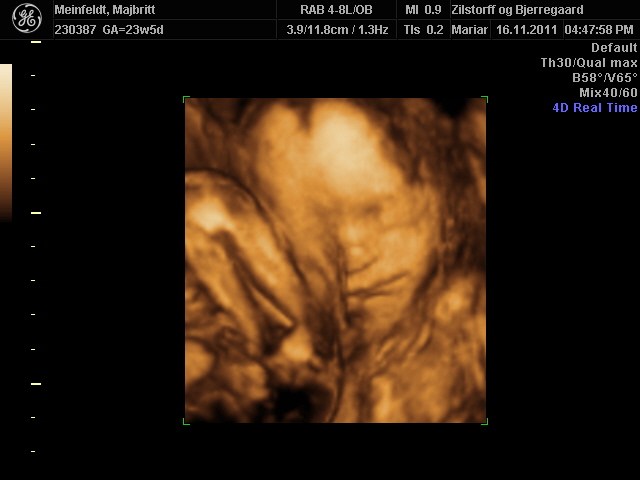

Hvor er det dejligt for jer, at have fået set jeres skønne børn.. Der er bare nogle rigtig fine billeder..

Vi har godt nok valgt ikke at få en 3D skanning, men man bliver helt varm om hjertet når man ser de fine billeder.. Og som der er skrevet længere oppe, der er jo lang tid til marts